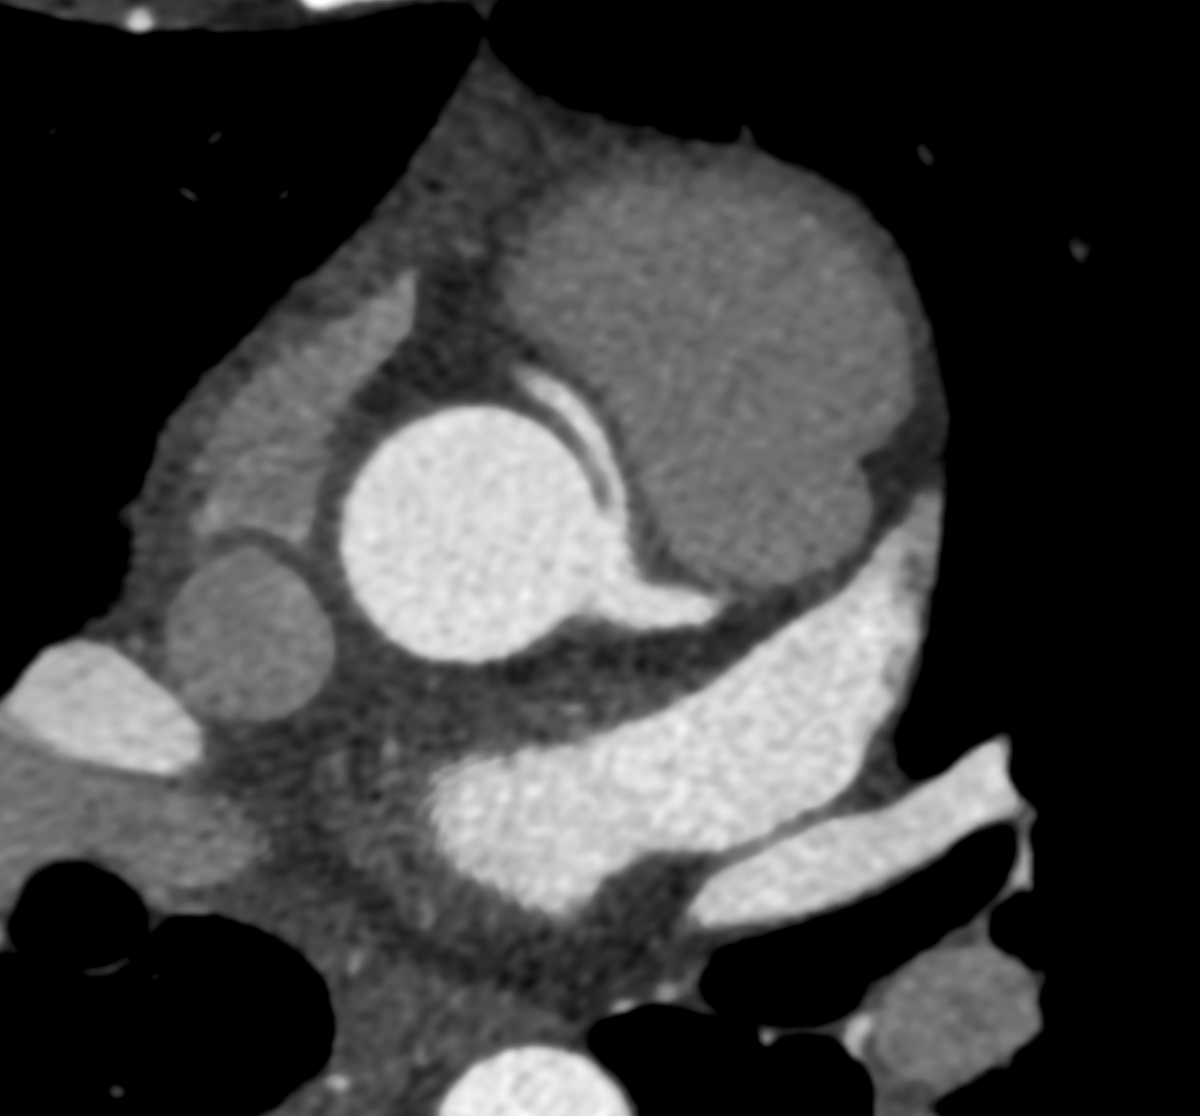

52-year-old male with severe aortic stenosis presents for preoperative assessment prior to transcatheter aortic valve replacement. Which side is preferable for access? #medstudent #cardiologist #heart #medical #medicine

0

1

7